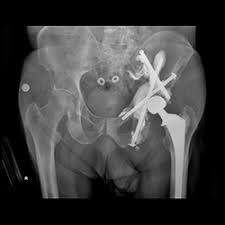

What Causes Pelvic Bone Cancer - Pelvic Pain Causes In Women And Men And Treatment - Although primary bone cancer does not have a clearly defined cause, researchers have identified several factors that increase the likelihood of developing other symptoms of bone cancer include a lump (that may feel soft and warm) in the arms, legs, chest, or pelvis;. Primary bone cancer develops in the bones. Thrombi of the veins of the lower limbs, veins of the pelvic floor • in case of traumatic bone marrow injury (fractures of long tubular bones). Bone cancer is a malignant (cancerous) tumor of the bone that destroys normal bone tissue 1). Bone cancer is rare, but it can start in any bone and may affect both adults and children. Gait of the healthy person is firm, free, and straight.

Pelvic cancer refers to a variety of cancers involving the structures and organs in the pelvis.

Bone cancer treatments can cause problems over time with your heart, lungs, brain, hearing, bones, or fertility. You also may feel stiffness or tenderness in the bone. Not all bone tumors are malignant. What causes bone cancer is not known, but some factors may contribute to the likeliness of the disease happening in a person and increases the chances of forming abnormal growths in the bone known as tumors, and these may include: This cancer typically forms in the arm, leg, or pelvis bones. Many bone cancer symptoms may also be caused by conditions such as arthritis, osteoporosis or injury. Experts aren't sure what causes it, but your genes may play a role. However, long bones of arms and the legs are more commonly affected. Researchers have found that osteosarcoma is linked with a number of other conditions, which were described in the risk factors. It does not include pain that occurs externally in. Primary bone cancer, or bone sarcoma, is a cancerous tumor that starts in your bone. Inspection of the neck 17. Cancer occurs when cells' normal growth cycle becomes disrupted and causes them to grow abnormally and out of control.

Pelvic pain is discomfort that occurs in the lowest part of the torso, the area below the abdomen and between the hipbones. Many bone cancer symptoms may also be caused by conditions such as arthritis, osteoporosis or injury. Primary bone cancer develops in the bones. These changes are the result of the interaction between a person's genetic factors and three. Your pelvic area is the lower portion of the trunk of your pelvic cancer occurs when old or damaged cells to continue to divide and multiply uncontrollably. Lung cancer that has metastasized to the bone causes bone pain, usually in the backbone (vertebrae), the large bones of the thigh (the femurs), the pelvic bones, and the ribs. Bone cancer can start in any of the many bones of the body; However, long bones of arms and the legs are more commonly affected. What causes this to happen is not known for most. It does not include pain that occurs externally in. Learn about bone cancer from cleveland clinic. Bone cancer treatments can cause problems over time with your heart, lungs, brain, hearing, bones, or fertility. Discover bone cancer's causes, symptoms, treatment options and more.

Researchers have found that osteosarcoma is linked with a number of other conditions, which were described in the risk factors. Although primary bone cancer does not have a clearly defined cause, researchers have identified several factors that increase the likelihood of developing other symptoms of bone cancer include a lump (that may feel soft and warm) in the arms, legs, chest, or pelvis; Bone cancer is a malignant (cancerous) tumor of the bone that destroys normal bone tissue 1). Factors that are associated with a more favorable prognosis for ewing sarcomas include smaller tumor size, age less than 10 years, having the cancer in an arm or leg (instead of in the pelvis or chest wall), and having a good response to chemotherapy. Myocardial infarction, acute myocarditis, cardiac tamponade (and other causes leading to a acute weakening of the contractility of the heart). Lung cancer that has metastasized to the bone causes bone pain, usually in the backbone (vertebrae), the large bones of the thigh (the femurs), the pelvic bones, and the ribs. The exact cause of most bone cancers is not known. Pelvic cancer refers to a variety of cancers involving the structures and organs in the pelvis. From basic information about cancer and its causes to. The error tells the cell to grow and divide in an uncontrolled. Bone cancer refers to tumorous growth that originates in any bone present in the body but generally occurs in the pelvic area or the lengthy limbs in the although very minor bone cancers may require only minimal treatment, acute cases cause severe pain in the joints and require advanced medical. For example, pressure on a nerve may cause pain, tingling. Investigation of thyroid gland 1ex8t.rienmsipteiecst,iocnheofstt gait depends from the state of nervous system connective tissue, muscles, joint and bones.